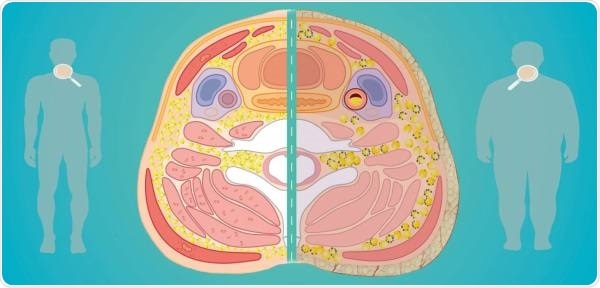

This simplified illustration demonstrates the researchers’ hypothesis about the morphological and cellular characteristics of the fat deposits in the neck, in a person of a normal weight who is relatively healthy vs. a person with obesity and associated comorbidities. This image is reproduced from the doctoral thesis published by Maria Jose Arias-Tellez on the Biomedicine programme of the University of Granada, entitled ‘Neck adipose tissue and neck circumference as predictors of cardiometabolic risk in sedentary adults’. Image Credit: University of Granada